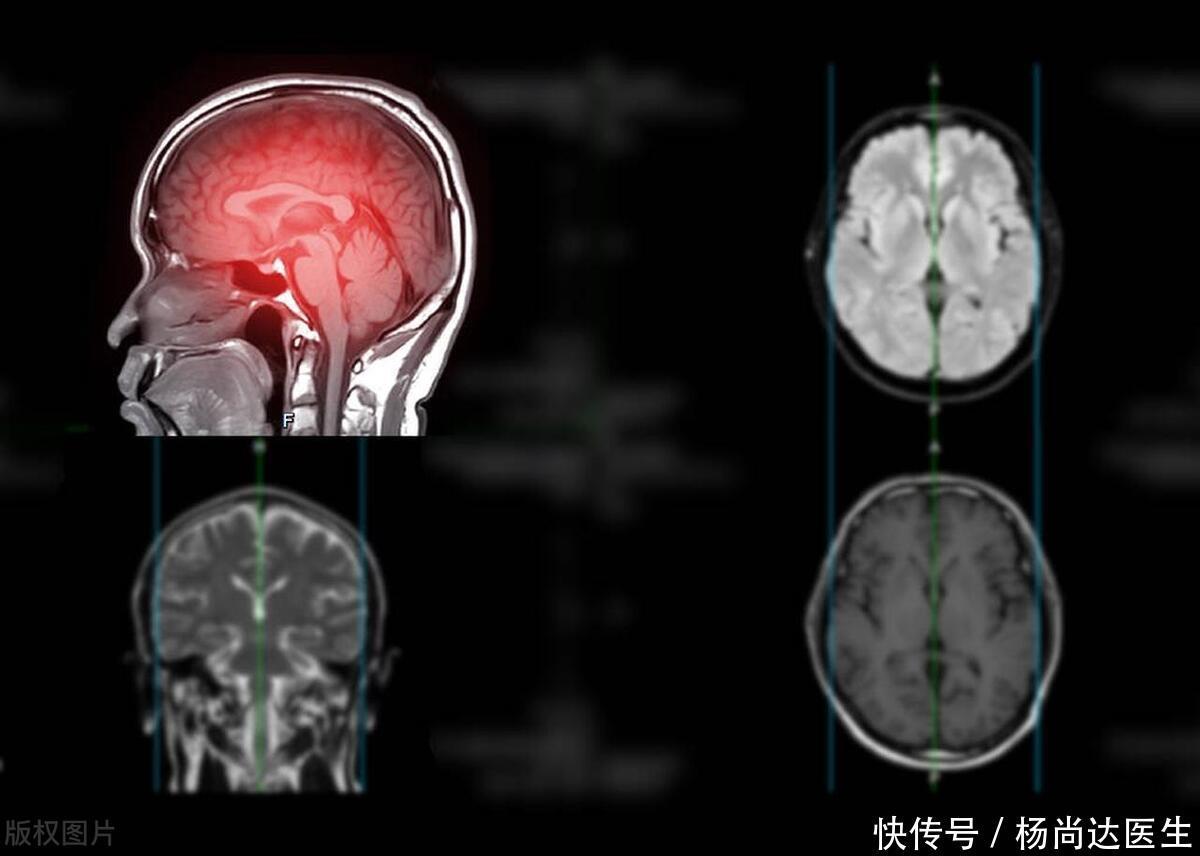

脑出血与急性脑卒中的诊断主要依赖于高精度的医学影像技术,如CT扫描和MRI成像。这些先进的医学影像技术,能够精确捕捉大脑内部的病变细节,为医生提供清晰的诊断依据,确保诊断的准确性。